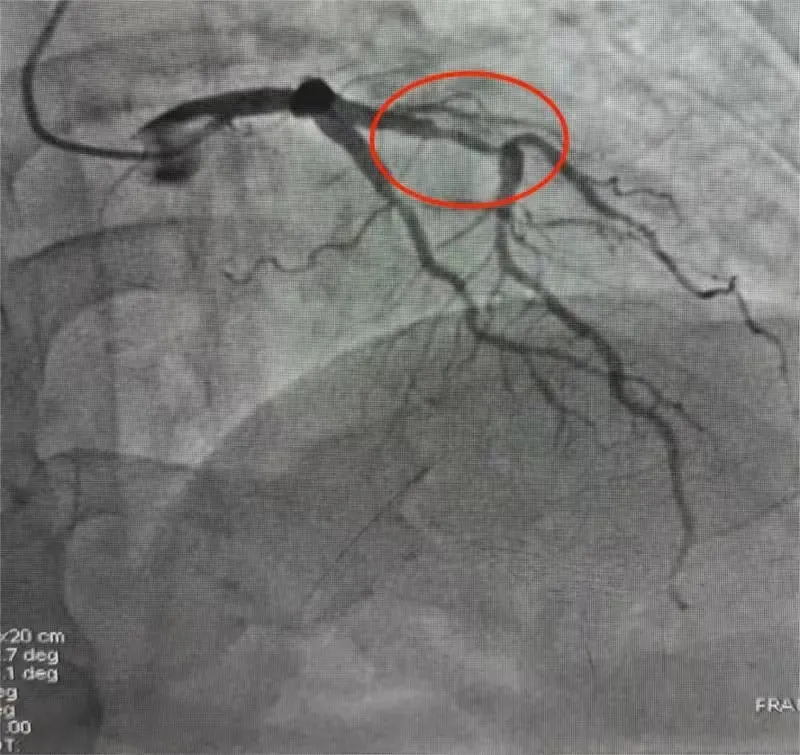

患者入院后,心脑血管康复科团队对患者进行完善的术前检查及评估并积极与其沟通,消除对方疑虑。经过充分的术前准备,心脑血管康复科主任孙春启及主治医师缪云鹏在介入导管室为患者实施冠状动脉造影术。术中发现该患者多支血管狭窄,最重达60%。

图1:冠脉造影检查图片